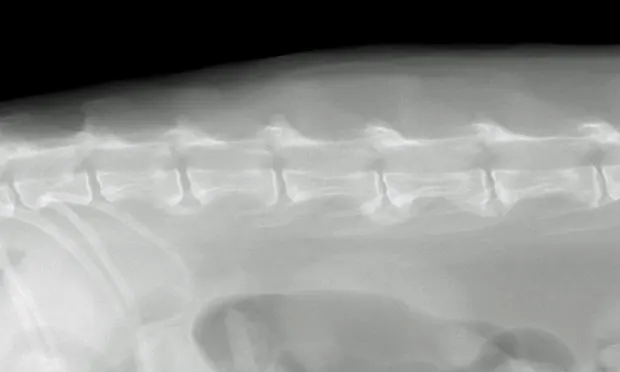

A lateral radiograph of a dog's spine shows a clear view of the vertebral column, highlighting the intervertebral discs and vertebrae. The image allows for assessment of potential abnormalities such as disc herniation or spinal alignment issues.

For conclusive proof of osteoarthritis, look for radiographic signs supportive of the loss of articular cartilage, osteophyte formation, bone remodeling, and inflammation along with cytology of joint fluid showing increased inflammatory cell counts and protein levels and decreased viscosity of fluid (see Laboratory Findings/Imaging for further discussion). Spondylosis deformans is diagnosed radiographically by identifying bony spurs of the fibrocartilagenous intervertebral joints of the spine (Figures 1 and 2).